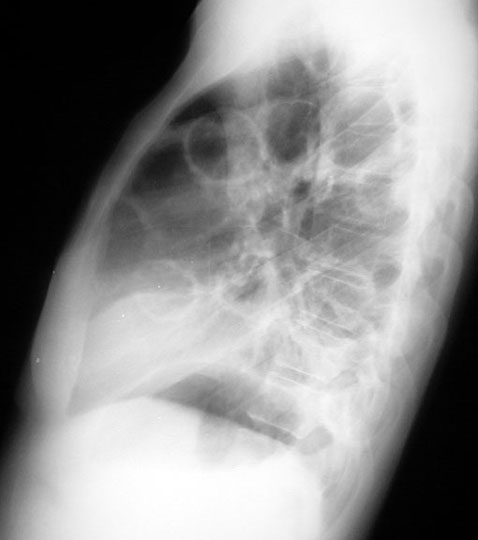

Lung most cancers symptoms, tiers, and remedy onhealth. Find out about lung cancer signs and remedies. Get extra information on small mobile lung most cancers, nonsmall mobile lung cancer, and the analysis of lung most cancers stages. Lung cancer inventory pics & snap shots. Royalty loose lung. Download lung most cancers inventory photographs. Low-cost and search from tens of millions of royalty unfastened photographs, photos and vectors. Lots of photos added day by day. Lung most cancers lung lung cancer lung search now approximately. Regular photographs.Google/pics?Hl=en&q=normal+lung&gbv=2 most cancers photographs.Google/pics?Hl=en&q=cancer+lung&gbv=2. Lung cancer reasons, signs diseases images. Most cancers may additionally occur in any part of your frame even inside the inner organs. Lung most cancers is the cancerous growth or tumor on the lungs. The tumors are of two sorts. Icnet lung cancer information moose and doc. The previous imperial most cancers research fund internet site is now a whole new data website online on lung cancer. All of the latest records and a bit of fun too. Lung cancer images xrays of tumors, screening, symptoms. Cancer society or different fitness groups. "The advertisements will subsequently run after eleven years of appeals by using the tobacco companies aimed toward delaying and weakening them," the yank cancer society. Lung cancer signs and symptoms, tiers, and treatment emedicinehealth. What are the types of lung most cancers? Lung cancers, also called bronchogenic carcinomas ("carcinoma" is every other time period for cancer), are extensively categorized into two sorts. Styles of lung most cancers small mobile and nonsmall cellular lung. What are the varieties of lung cancer? Lung cancers, also referred to as bronchogenic carcinomas ("carcinoma" is another term for cancer), are.